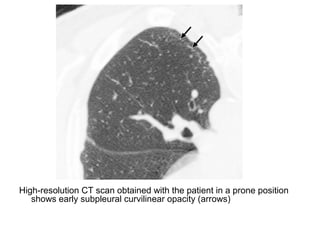

-HRCT :

*An early feature is a subpleural curvilinear opacity, this

finding represents peribronchiolar fibrosis

Axial high-resolution CT scan shows a subpleural curvilinear opacity

(arrows) thought to represent peribronchiolar fibrosis

High-resolution CT scan obtained with the patient in a prone position

shows early subpleural curvilinear opacity (arrows)